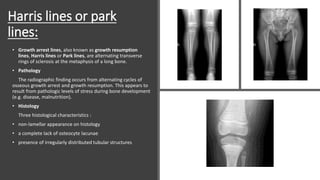

Harris lines or park

lines:

• Growth arrest lines, also known as growth resumption

lines, Harris lines or Park lines, are alternating transverse

rings of sclerosis at the metaphysis of a long bone.

• Pathology

The radiographic finding occurs from alternating cycles of

osseous growth arrest and growth resumption. This appears to

result from pathologic levels of stress during bone development

(e.g. disease, malnutrition).

• Histology

Three histological characteristics :

• non-lamellar appearance on histology

• a complete lack of osteocyte lacunae

• presence of irregularly distributed tubular structures